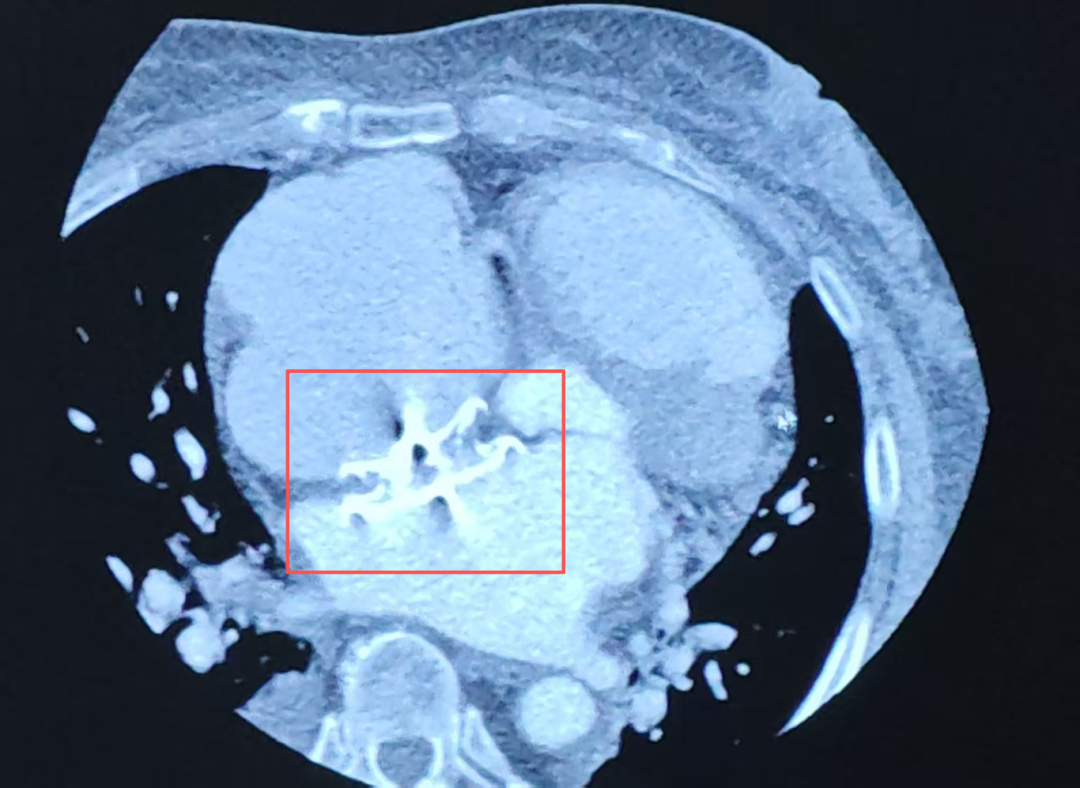

10多年前,李伯曾做过房间隔缺损封堵介入手术。如今,这枚植入的房间隔封堵器已经完全内皮化,像一面光滑坚韧的“合金之墙”,封堵了所有常规穿刺路径。

房间隔封堵器挡住了介入手术的必经之路

更棘手的是,直接穿刺封堵器本体这个预设方案,也遭遇了前所未有的阻力:无论是专用穿刺针还是加强穿刺针,都没办法在这面致密的“墙”上建立哪怕一个突破点。